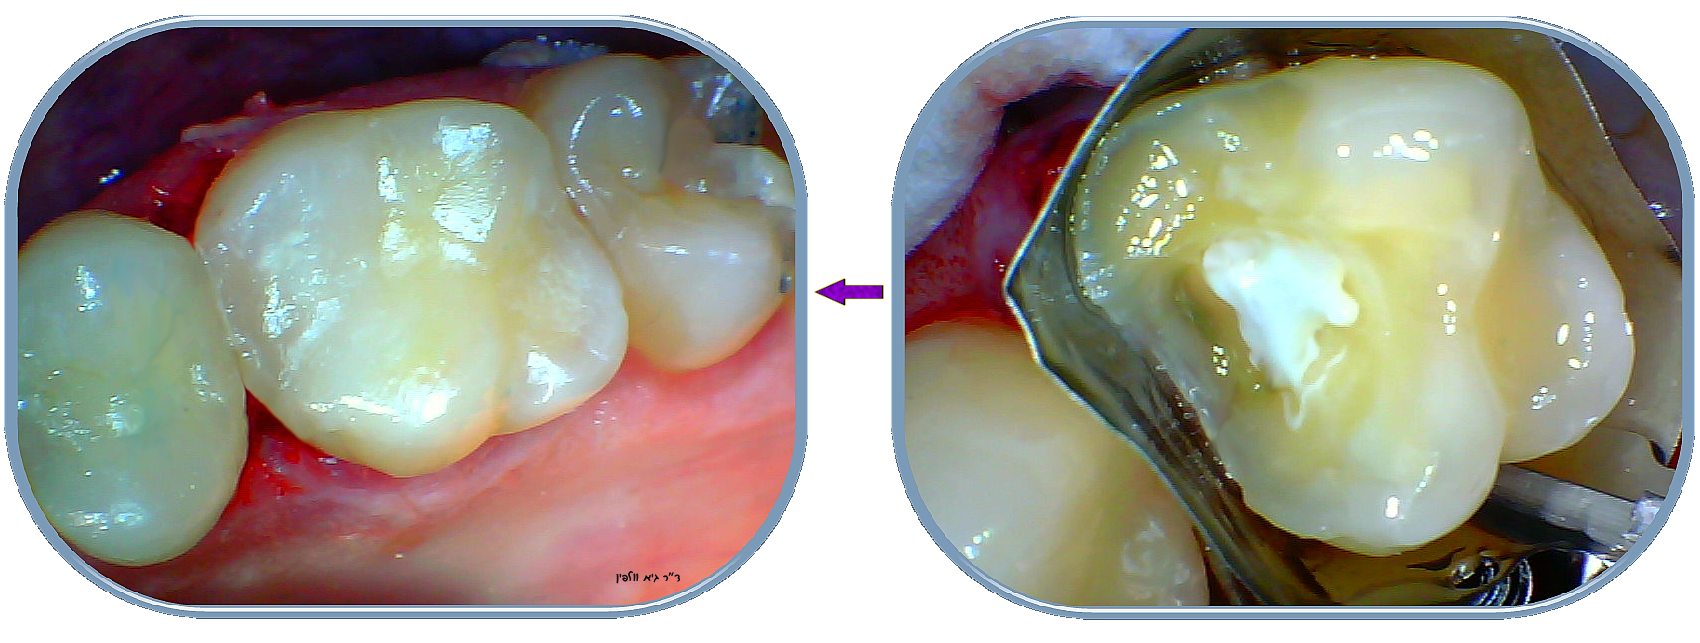

בתהליך כיפוי (=כיסוי) המוך, במידה והרופא איבחן שיש חור מאוד עמוק אך ככל הנראה עוד אין דלקת בעצב, רופא מנוסה ושמרני ינסה להציל את השן ולא מיידית להחליט על טיפול שורש או רק לעשות "סתימה": הרופא מורח באיזור העמוק ביותר חומרים מיוחדים שתפקידם לחסל חיידקים ולחזק את האיזור, ולבודד את איזור העצב שנחשף מחשיפה לאוויר ולחיידקים, למשל Theracal שמעודד בניית השן מחדש באיזור הפנימי ע"י שיחרור  calcium silicate וחומרים אנטיבקטריאליים אחרים. כמו כן נמרחים גם חומרים אחרים לחיטוי/ניקוי/הפחתת הרגישות שאופיינית לחורים עמוקים מאוד.

רק לאחר ביצוע כיפוי המוך ימשיך הרופא ויבצע את שיחזור השן והאנטומיה המקורית. כיפוי המוך הנ"ל משפר את הסיכוי של הצלחת הסתימה, לעומת סתימה "רגילה" עמוקה וללא כיפוי מוך. כמובן כל זאת בתנאי שעדיין לא מתפתח דלקת בעצב, נמק או זיהום.